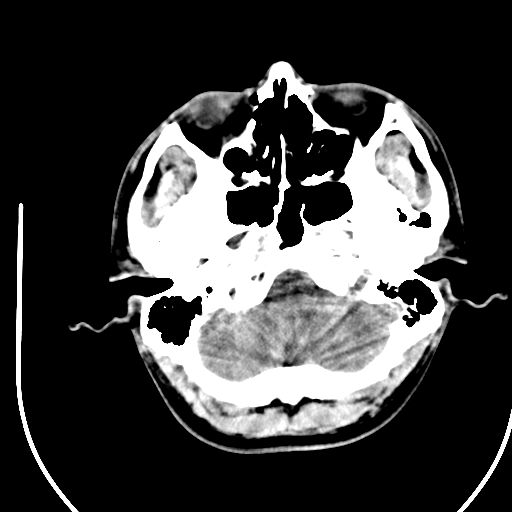

标题: CT28158:男,27Y。头痛数月,左顶叶血管瘤。 [打印本页]

标题: CT28158:男,27Y。头痛数月,左顶叶血管瘤。

考虑avm。

考虑avm。  建议dsa检查。

海绵状血管瘤

考虑左顶叶海绵状血管瘤,建议mr检查。

左侧额叶海绵状血管瘤可能性大;建议行mri检查。

考虑血管畸形,因其周可见水肿,不除外感染性病灶。建议mri检查。